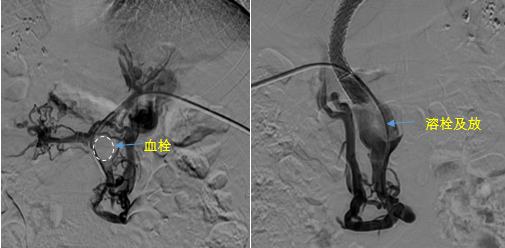

在西安國(guó)際醫(yī)學(xué)中心醫(yī)院,韓國(guó)宏教授對(duì)李女士進(jìn)行了細(xì)致的問(wèn)診及檢查,在CT圖像上仔細(xì)的分析,針對(duì)患者特殊的病情制定了詳細(xì)的治療方案。第一次進(jìn)入手術(shù)室,在DSA的監(jiān)測(cè)下,造影過(guò)程中門靜脈血栓的輪廓逐漸顯現(xiàn)出來(lái),見(jiàn)多識(shí)廣的醫(yī)生們也大吃一驚,發(fā)現(xiàn)遠(yuǎn)端脾靜脈及腸系膜上靜脈也存在大量血栓?;颊叩氖彻芪傅嘴o脈曲張非常嚴(yán)重,疏通堵塞的門靜脈已是刻不容緩。

見(jiàn)此情形,韓國(guó)宏教授憑借豐富的臨床經(jīng)驗(yàn)很快調(diào)整了策略,在超聲診療中心的協(xié)助下進(jìn)行門靜脈右支穿刺,并進(jìn)行造影,看到目標(biāo)血管后,韓國(guó)宏教授用“明修棧道,暗渡陳倉(cāng)”的方法,讓來(lái)自脾臟和胃腸的血流終于暢通的回流到了肝靜脈。通過(guò)血流的沖刷以及抗凝溶栓藥物的作用,幾日后復(fù)查造影發(fā)現(xiàn)門靜脈血栓已逐漸變小,不會(huì)對(duì)回流到肝臟的血流產(chǎn)生大的阻礙作用,門靜脈的壓力顯著減小,患者再次出血的幾率也隨之降低。幾經(jīng)周折,這顆“定時(shí)炸彈”終于被拆除,李女士和她的家人多年來(lái)心里的石頭也終于落地。